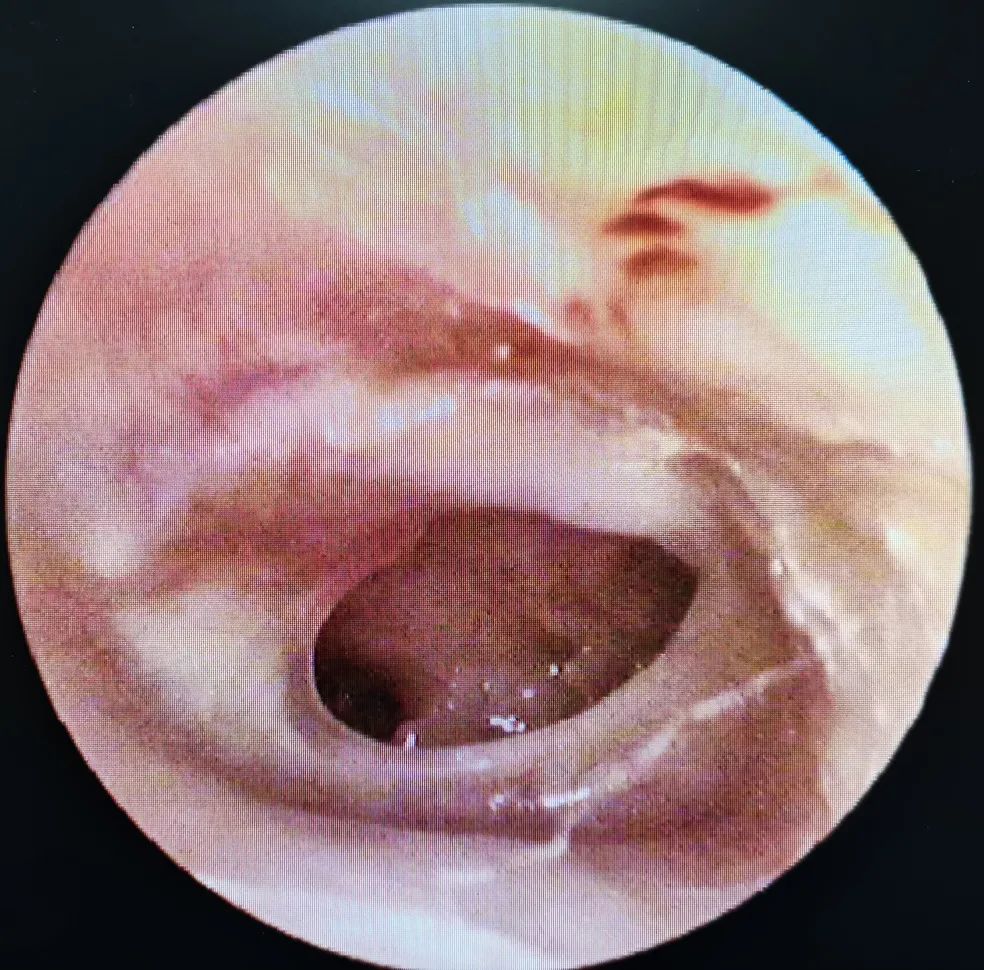

原来耳膜是这样的,偶尔有点痛,发红了像发炎

【名医坐诊】长期耳痛,耳流脓?小心耳朵里的"破坏大王"